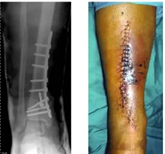

Vad ser du på bild, vad är felet?

A

• Vänster humerusfraktur har mkt callus men den dockar inte ihop är tecken på att den behöver stabilitet. För mkt strain

o Hypertrof pseudartros

• Radiusfraktur till höger där det inte händer något. För dålig mekanisk stabilitet och för lite biologi. Usel strain på radius med det de satt in (räcker inte)

o Atrofisk pseudartros